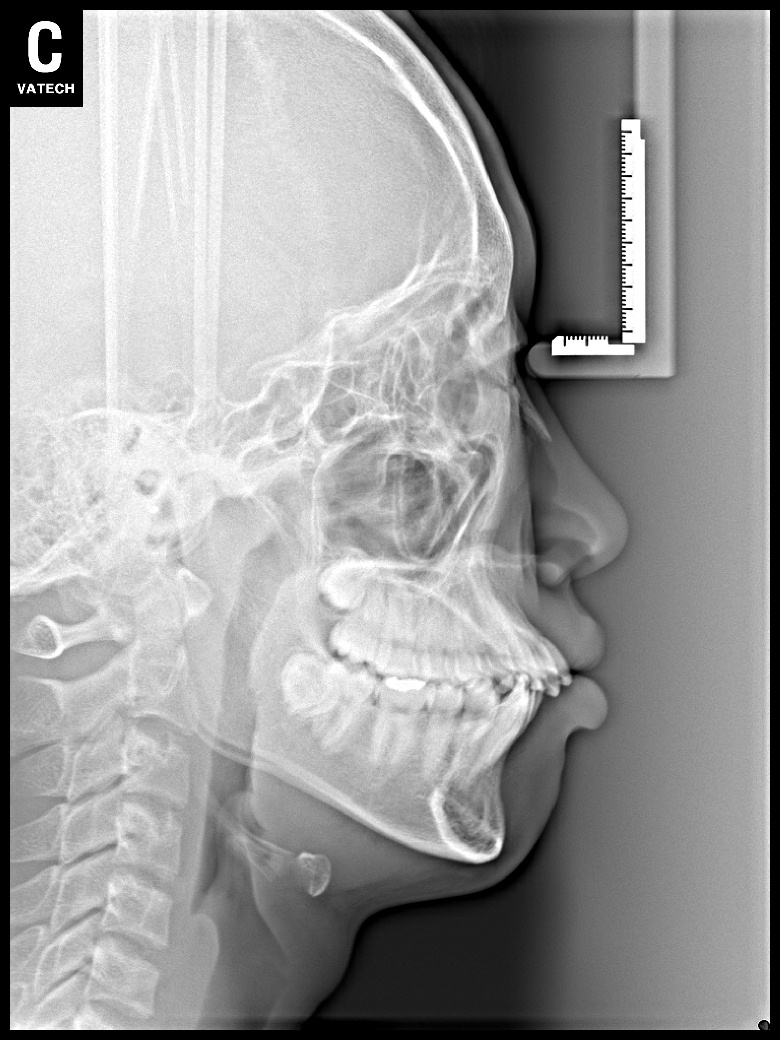

치료 후 사진입니다.